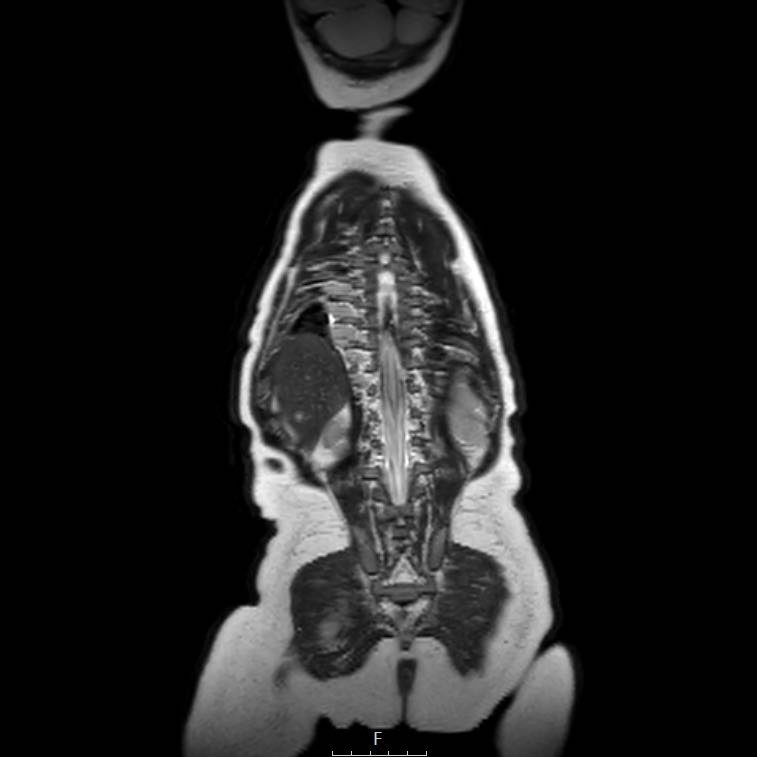

Cuộn qua chuỗi ảnh T2 theo mặt phẳng coronal.

Nghiên cứu các hình ảnh và sau đó tiếp tục đọc.

The findings are:

- Mass with encasement of the aorta and splanchnic vessels.

- Lan rộng dọc theo cột sống ngực nhưng không xâm lấn vào ống sống.

- Small liver metastases.

- Left supraclavicular mass.

Same patient.

Mức độ lan rộng của khối u được đánh giá rõ ràng trên chuỗi xung TSE T2 weighted 3D theo mặt phẳng axial.

The left kidney is compressed and displaced caudally.

Có di căn hạch bạch huyết cạnh động mạch chủ (mũi tên vàng nhỏ).

Nguyên ủy của thân tạng và động mạch mạc treo tràng trên bị khối u bao quanh (đầu mũi tên).

Tĩnh mạch chủ dưới bị đẩy ra phía trước (mũi tên xanh).

Xẹp phổi hai bên ở vùng lưng thường được thấy trên MRI, vì việc kiểm tra được thực hiện dưới gây mê.